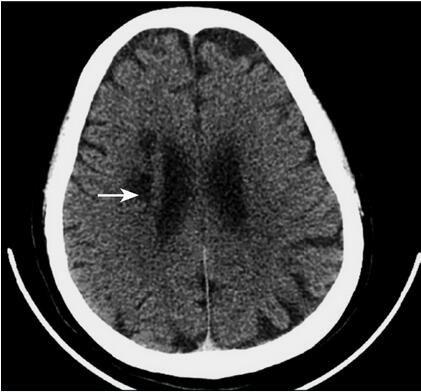

1小时条评论1 病例简介 患者男,79岁,急诊以右侧肢体轻度活动不利伴发作性双目无神19日于2009年2月12日入院。 现病史:2009年1月25日晚轻微活动中突发意识丧失、面色苍白,当时无肢体抽搐、两便失禁、两眼上翻,约10分钟自行清醒,立即来我院急诊,行颅脑CT检查为多发性腔隙性...